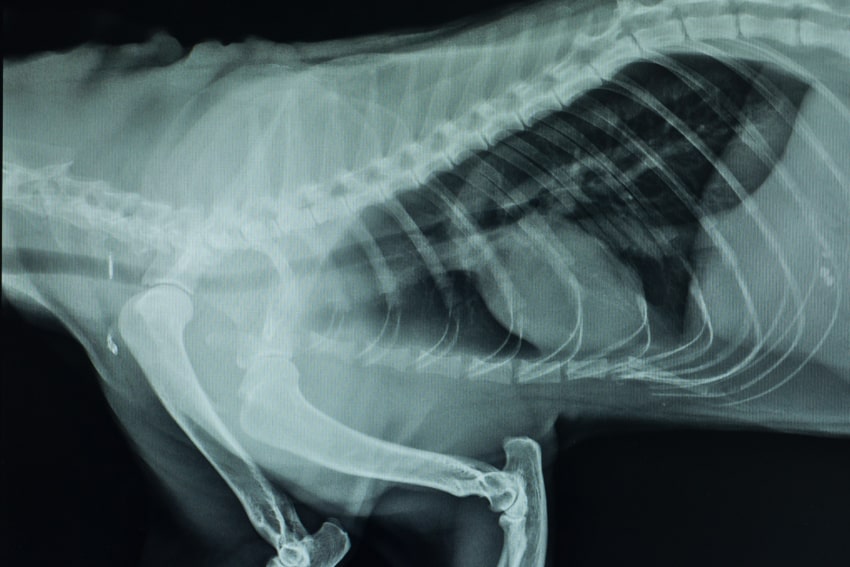

x-ray image

X-rays and Ultrasound Imaging Tests

X-rays are used to evaluate the size and shape of internal organs, such as the heart and lungs, as well as to demonstrate broken bones, arthritic changes in the joints, some foreign objects in the gastrointestinal tract, stones in the urinary bladder, tumors in the abdomen and thorax, fluid accumulations in the abdomen (belly) and thorax (chest), and many more abnormalities that may aid in diagnosis of your pets illness. It is also the most affordable imaging test, and is most often done prior to any of the other imaging options.